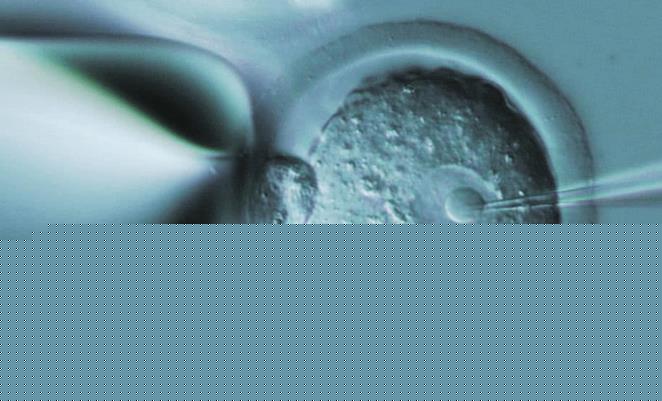

有些女性由于身体原因无法使用自身卵子,或者卵子质量低,导致无法受孕。这时,选择供卵三代试管技术可以解决这一问题。同时,供卵三代试管技术可以避免一些常见的遗传病传递给下一代,提高了孩子健康的概率。